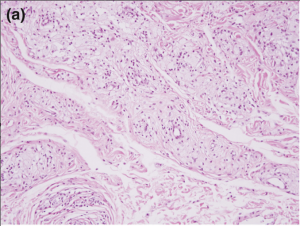

Biopsy:

Reticular dermis infiltration of foamy macrophages with sparing of the epidermis, papillary dermis, and subcutaneous fatty layer. The inflammatory infiltrate in the superficial reticular dermis will be perivascular and consist of foam cells with lipid-laden cytoplasmic vacuoles [5]. Foam cells, or xanthoma cells, originate from macrophages that have accumulate intracellular cholesterol, lipids, and fat [7][8].